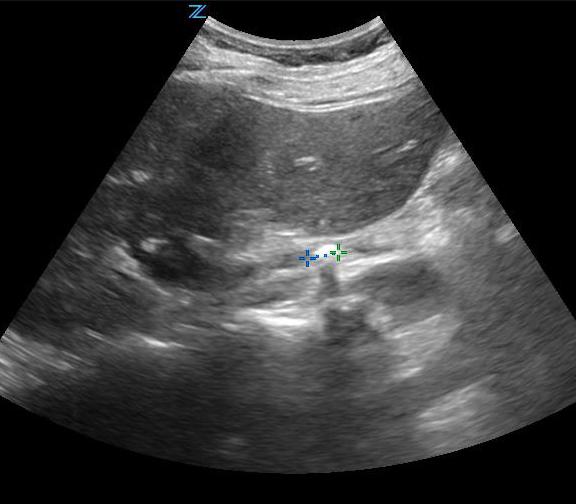

- Figure 2. Moderate hydronephrosis demonstrating location of ureter (surrounded by arrows) exiting renal pelvis

- The primary sonographic abnormality you will identify in the patient with suspected renal colic is hydronephrosis. The degree of hydronephrosis relates to the degree and extent of obstruction: (Illustration 2, Videos 11-17)

- After complete obstruction to flow, there is an acute rise in intrarenal pressure. The renal pelvis and calyces dilate first. On US you will see echo-free areas distending the normal bright (echogenic) central area of the kidney.

- As obstruction continues, the renal parenchyma becomes compressed and you see thinning of the pyramids.

- Videos 14-15. Moderate hydronephrosis